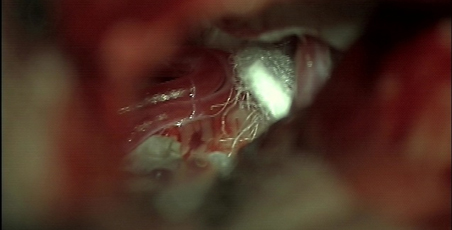

Through a small opening behind the ear, Dr. Bederson exposed the trigeminal nerve at its entrance into the brain stem. Here he found it severely compressed by both an abnormal arterial loop and vein.

Dr. Bederson moved the blood vessels off the trigeminal nerve and used a small sponge to keep them apart.